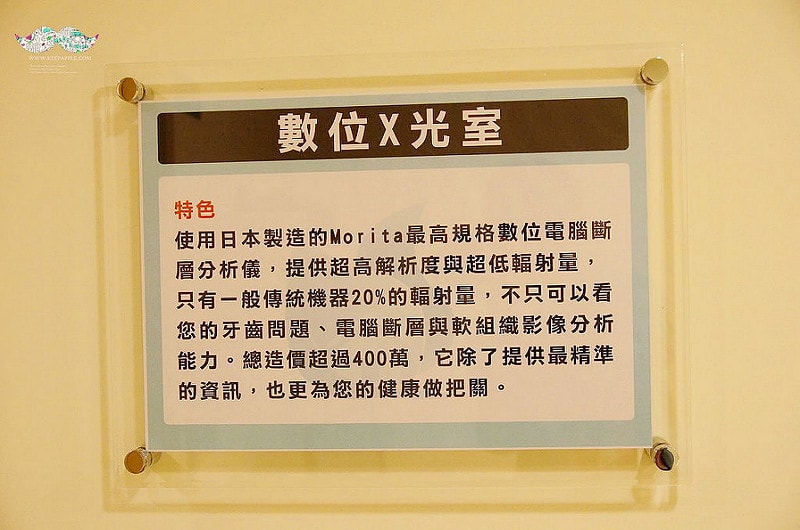

最新的數位X光室裏頭的電腦斷層分析儀

可以把牙齒內部構造都給照得非常清晰

掃描出病患整個上下顎的模型圖

重點是只有一般傳統機器20%的輻射量喔!

上次來看牙齒我也照了

機器轉個圈意外的很快一下就好了XD